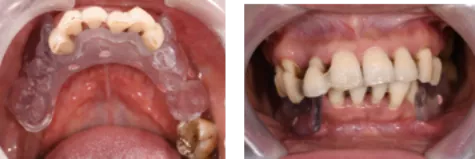

口内检查

· 下颌多颗后牙缺失 ,上下前牙成扇形排列,余留牙除上中切牙 1度松动外,其余牙均2-3度松动。

无牙颌固定修复存在美学风险

§ 义龈部分与软组织的边缘线在大笑时位于唇线以下为高分险(HER),应将其置于唇线以上以降低美学风险。患者为高笑线,因此需要截骨,截骨线应位于患者最大笑时唇线以上4mm。